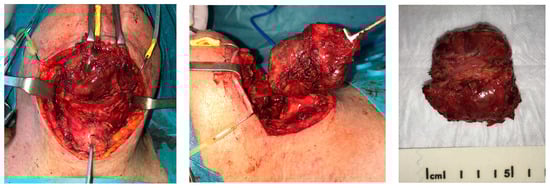

After pathological diagnosis, mass excision surgery was performed under general anesthesia, according to the multidisciplinary tumor board recommendation. Informed consent was obtained from the patient. Surgery consisted of the hyoid resection of the tumor enlarged to suprahyoid and subhyoid muscles. Afterward, a tracheotomy and installation of the Portex-type tracheal cannula were performed, and a nasal feeding tube was inserted (Figure 5).

Figure 5. Hyoid resection of the tumor enlarged to suprahyoid and subhyoid muscles.